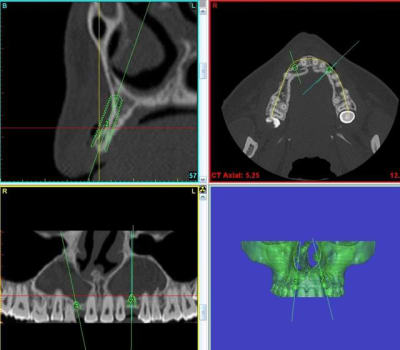

et celui là, vous le sentez comment?

précision...cette jeune femme a quand même 9 agénésies...

Pour 12 et 22

Greffe onlay bloc autogène ligne oblique

Implants 5 mois plus tard

Ajout conjonctif au besoin, souvent mieux au final

oui Céramik, c'est le plan de ttm idéal dans l'absolu...

mais...les 9 agénésies ne sont pas sans conséquences sur la morphologie osseuse dans la zone des DDS inf...bilan, très peu de nonos utilisable donc 2 sites de prélèvement + 2 sites op...çà fait beaucoup...bilan: direction biobank et 2 blocs...;-)